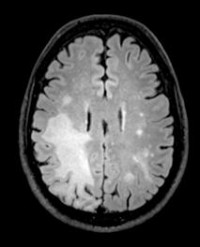

The status of their infection was monitored by MRI scans of their brains and by checking the levels of JCV in their cerebral spinal fluid (CSF).

Importantly, these patients' symptoms improved or stabilsed, and their brain MRIs showed shrinking of infection-related brain lesions.

Image credit: Irene Cortese